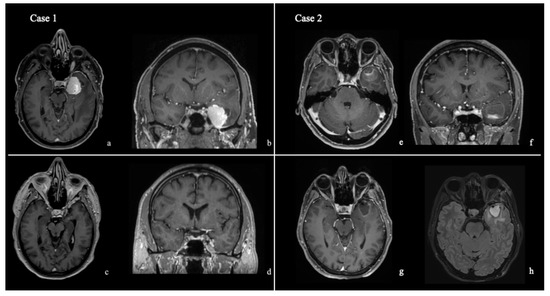

Giant Right Sphenoid Wing Meningioma as a Reversible Frontal Network Lesion: A Pseudo-bvFTD Case with Venous-Sparing Skull-Base Resection

Background and Clinical Significance: Giant sphenoid wing meningiomas are generally viewed as skull base masses that compress frontal centers and their respective pathways gradually enough to cause a dysexecutive–apathetic syndrome, which can mimic primary neurodegenerative disease. The aim of this report is to illustrate how bedside phenotyping and multimodal imaging can disclose similar clinical presentations as surgically treatable network lesions. Case Presentation: An independent, right-handed older female developed an incremental, two-year decline of her ability to perform executive functions, extreme apathy, lack of instrumental functioning, and a frontal-based gait disturbance, culminating in a first generalized seizure and a newly acquired left-sided upper extremity pyramidal sign. Standardized neuropsychological evaluation revealed a predominant frontal-based dysexecutive profile with intact core language skills, similar to behavioral-variant frontotemporal dementia (bvFTD). MRI demonstrated a large, right fronto-temporo-basal extra-axial tumor attached to the sphenoid wing with homogeneous postcontrast enhancement, significant vasogenic edema within the frontal projection pathways, and a marked midline displacement of structures with an open venous pathway. With the use of a skull-base flattening pterional craniotomy with early devascularization followed by staged internal debulking, arachnoid preserving dissection, and conservative venous preservation, the surgeon accomplished a Simpson Grade I resection. Sequential improvements in the patient’s frontal “re-awakening” were demonstrated through postoperative improvements on standardized stroke, cognitive and functional assessment scales that correlated well with persistent decompression and symmetric ventricles on follow-up images. Conclusions: This case illustrates the possibility of a non-dominant sphenoid wing meningioma resulting in a pseudo-degenerative frontal syndrome and its potential for reversal if recognized as a network lesion and treated with tailored, venous-sparing skull-base surgery. Contrast-enhanced imaging and routine frontal testing in atypical “dementia” presentations may aid in identifying additional patients with potentially surgically remediable cases. Full article

Figure 1